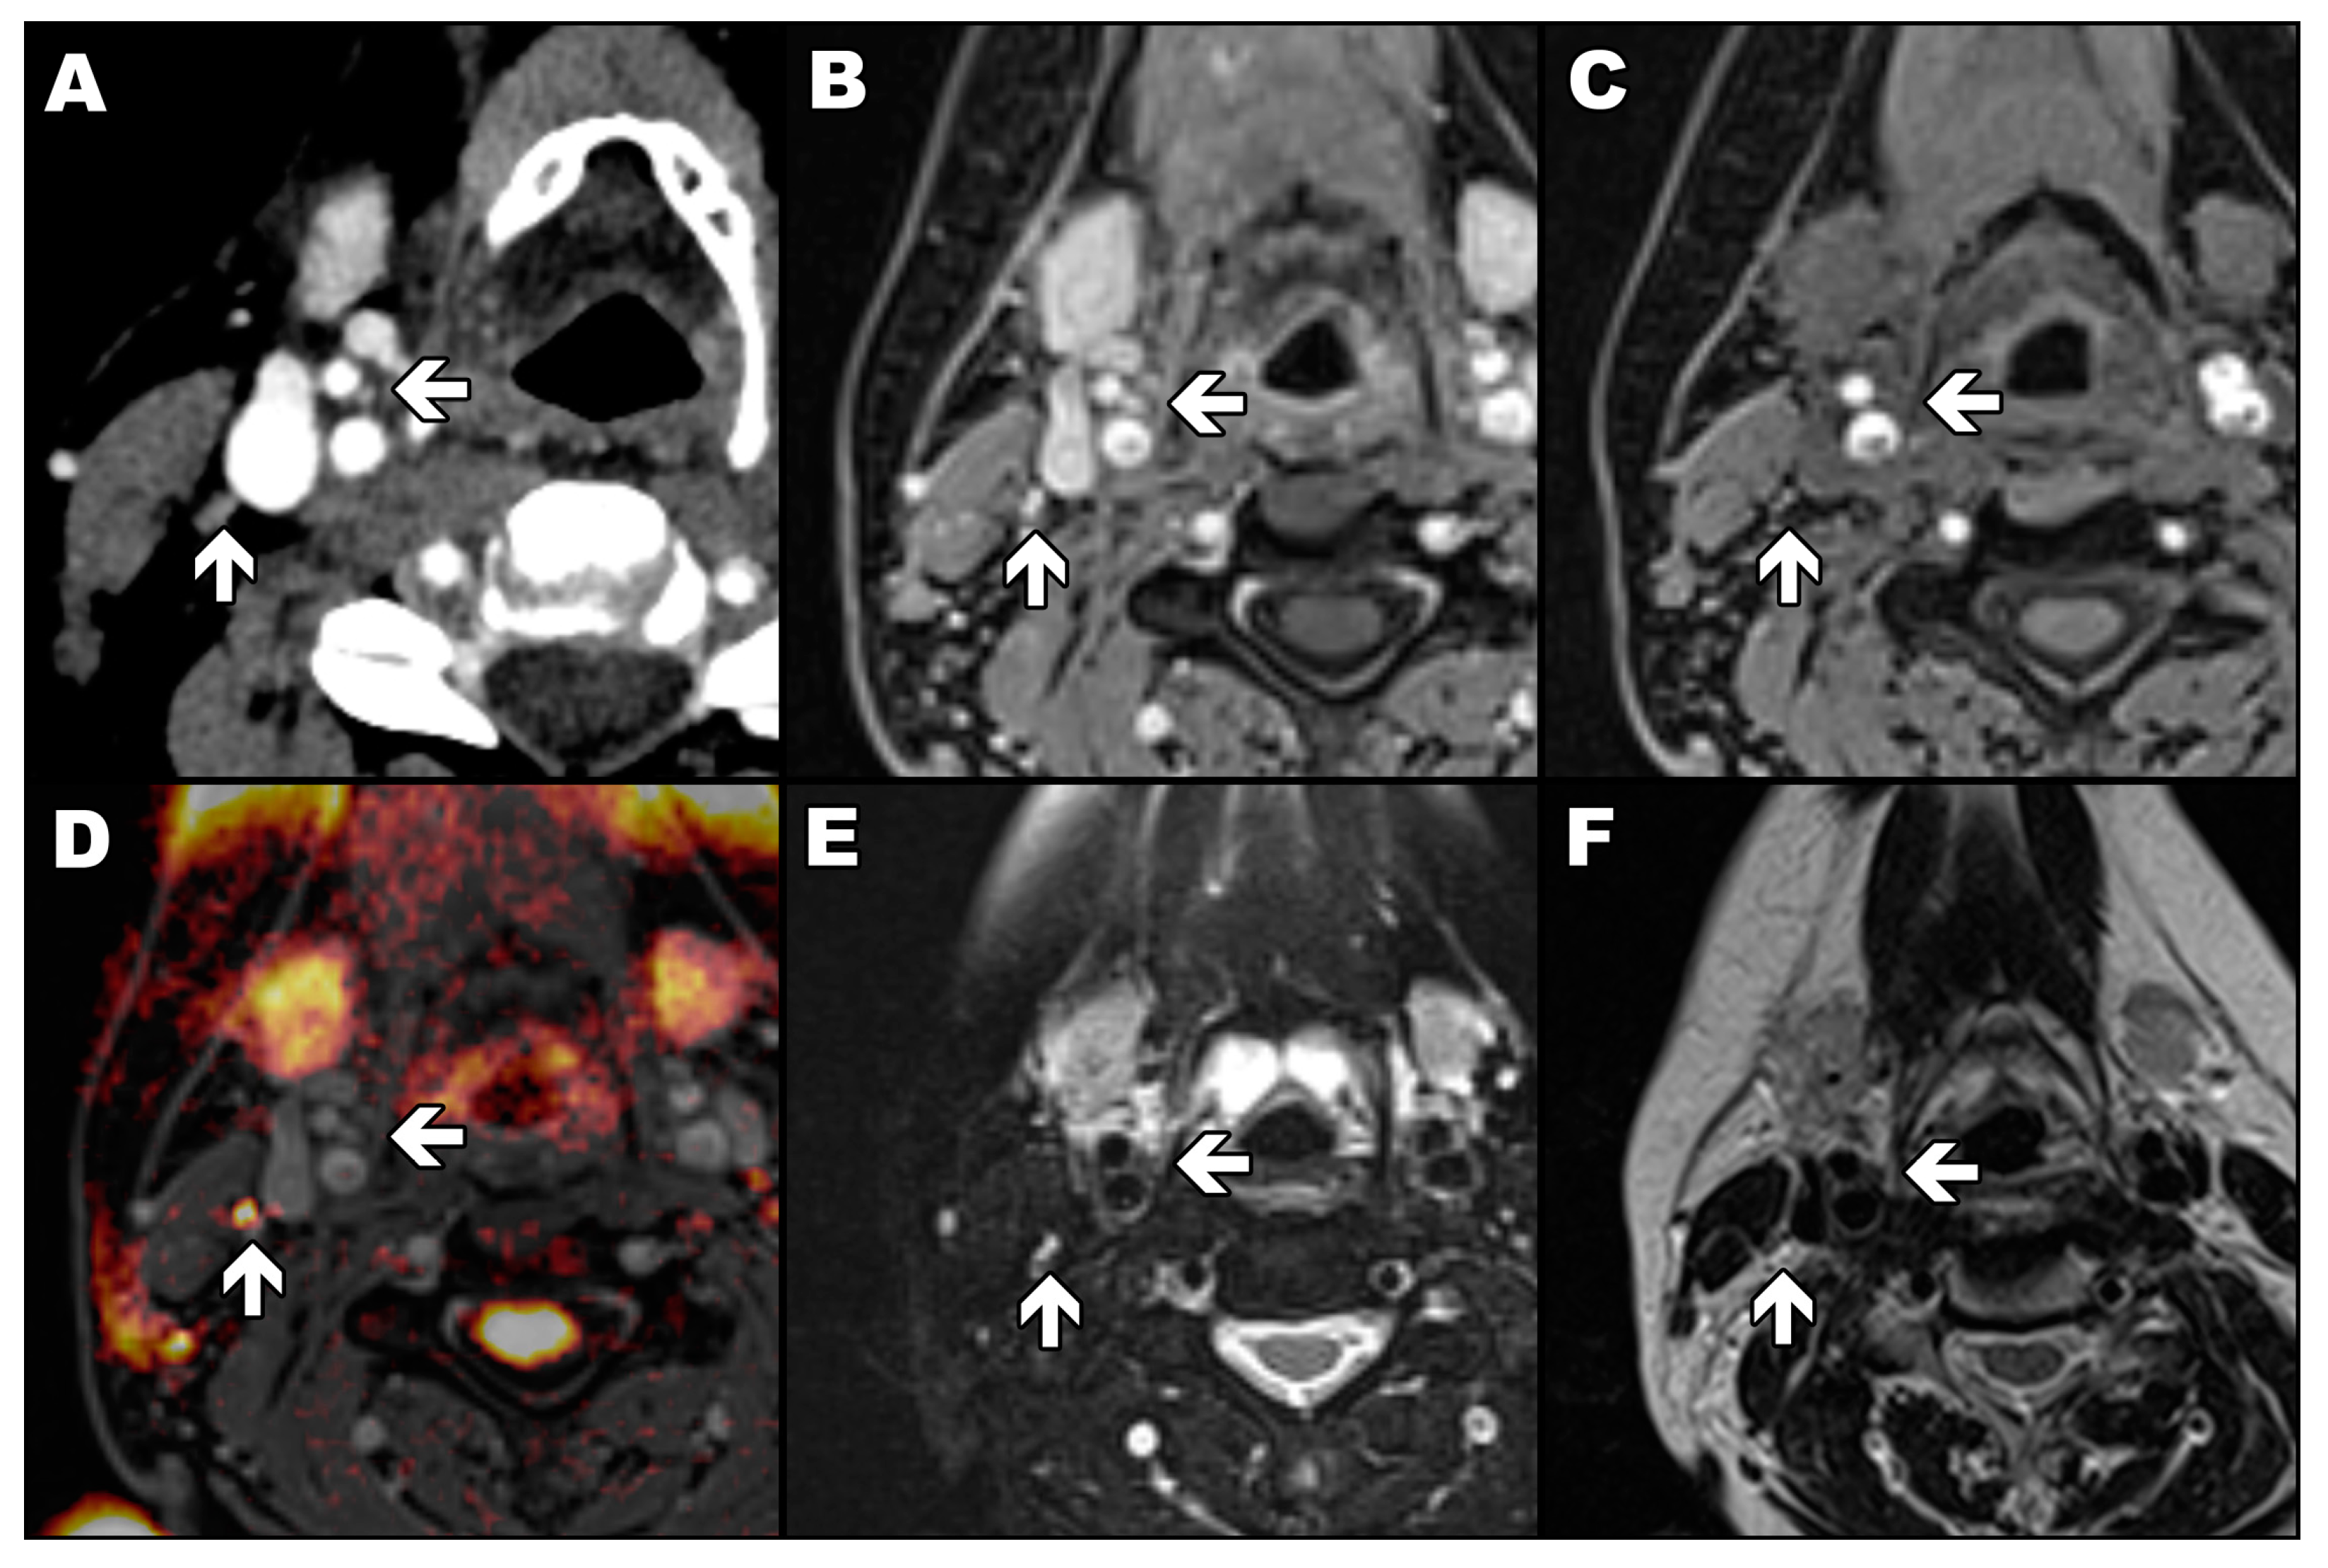

The readout-segmented echo-planar diffusion-weighted sequence with b values of 0, 500 and 1000 s/mm2, slice thickness of 5.0 mm, gap of 1.0 mm, and pixel size of 1.5 × 1.5 mm was acquired with parallel imaging technique (GRAPPA, acceleration factor of two). The sequence was used only to differentiate CBs from potentially adjacent lymph nodes (Figure 1). Only a diffusion-weighted image allows a lymph node to be easily distinguished from a carotid body as the first one has a high signal (yellow) and the second has a low signal (Figure 1D). In the rest of the presented magnetic resonance images, a lymph node and a carotid body have a similar appearance.

Figure 1.

Signal characteristics of the carotid body and lymphatic node. Arrows mark the carotid body (←) and lymph node (↑). Axial contrast-enhanced computed tomography image of the patient with marked carotid body and lymph node (A); VIBE sequence in T1-weighted image with Dixon technique in the water-only image with (B) and without (C) contrast agent enhancement; diffusion-weighted image with b value of 1000 s/mm2 automatically fused with contrasted-enhanced VIBE sequence in T1-weighted image with Dixon technique in the water-only image (D); turbo spin-echo sequence in T2-weighted image with (E) and without (F) fat saturation.